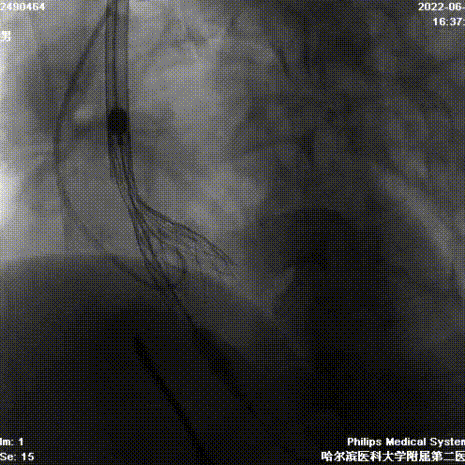

造影检查入路

根部造影

球囊预扩

首次释放

二次释放

瓣膜释放完成

术中回收释放两次,释放过程中预估瓣叶增厚挤压瓣架的偏移下滑程度,适当调整瓣架初始植入深度,结合经颈动脉入路而对输送系统产生的血流冲击力适时调整输送系统和导丝张力,保证最大的同轴性,从而保证人工瓣膜充足且温和的锚定和脱钩时的最小形变。